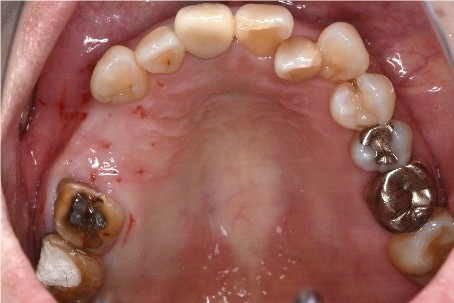

女性Tさん 60代(インプラント)

主訴

上の前歯の部分入れ歯が合わないので、インプラントにしたい。

治療内容

インプラントを4本埋入しました。

所感

骨の厚みが薄かったのですが、X-Guideを用い、正確に埋入することが来ました。

治療後「とてもきれいに出来てうれしかったです。話をしても、空気がもれず良くなりました。もう少し早く治すと良かったと思いました。」と、とても喜んでくださいました。

インプラント4本:¥363,000×4本=¥1,452,000(税込)

Before

インプラント埋入前

義歯を装着したところ

使用していた部分入れ歯

After

インプラント埋入後